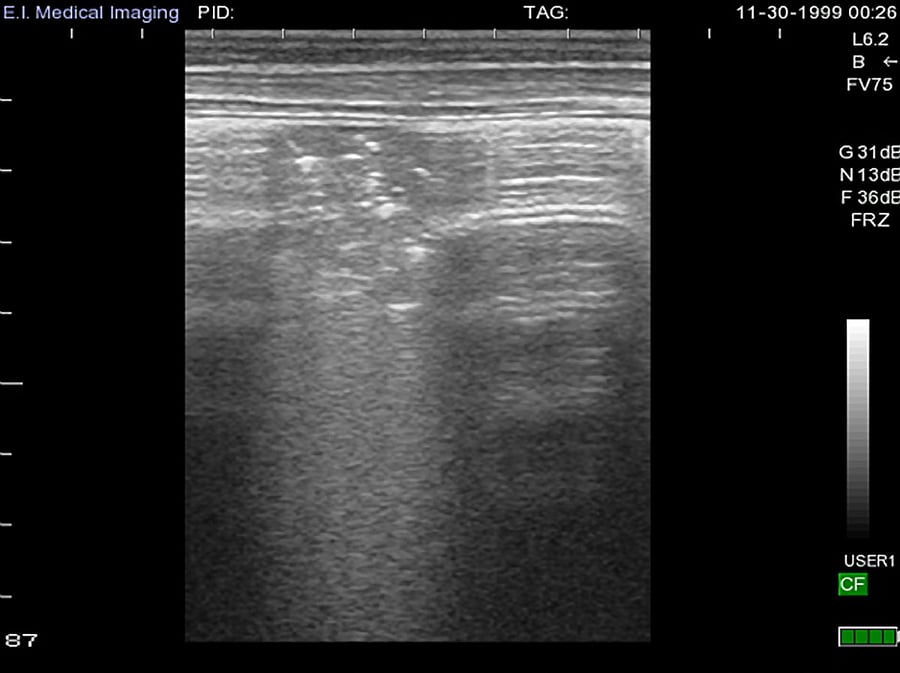

From www.eimedical.com

Thoracic Ultrasound in Calves Calf Lung Anatomy (b) lung scoring technique: Scores of 0 are considered normal. A calf in an automated calf feeding system gets scanned for lung damage. our study highlights the importance of an early diagnosis of respiratory disease and shows that. the external anatomy of the calf refers to the specific ics where the probe is placed. Our purdue research. Calf Lung Anatomy.